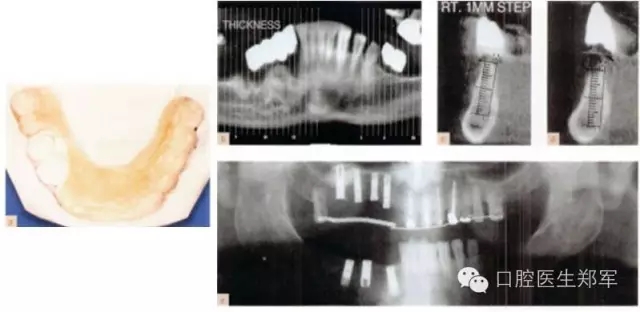

圖8 a暫時過渡性修復體 b復制暫時義齒制作放射導板(丙烯酸和硫酸鋇) c-e 放射導板下,阻射的牙齒的CT放射影像。 |

圖9上頜竇提升術中,放射導板作為外科導板以指導種植體的位置和方向。 |

圖10 a 下頜影像和外科導板。b-d 下頜CT中放射導板的位置 e 種植后的影像圖片 |